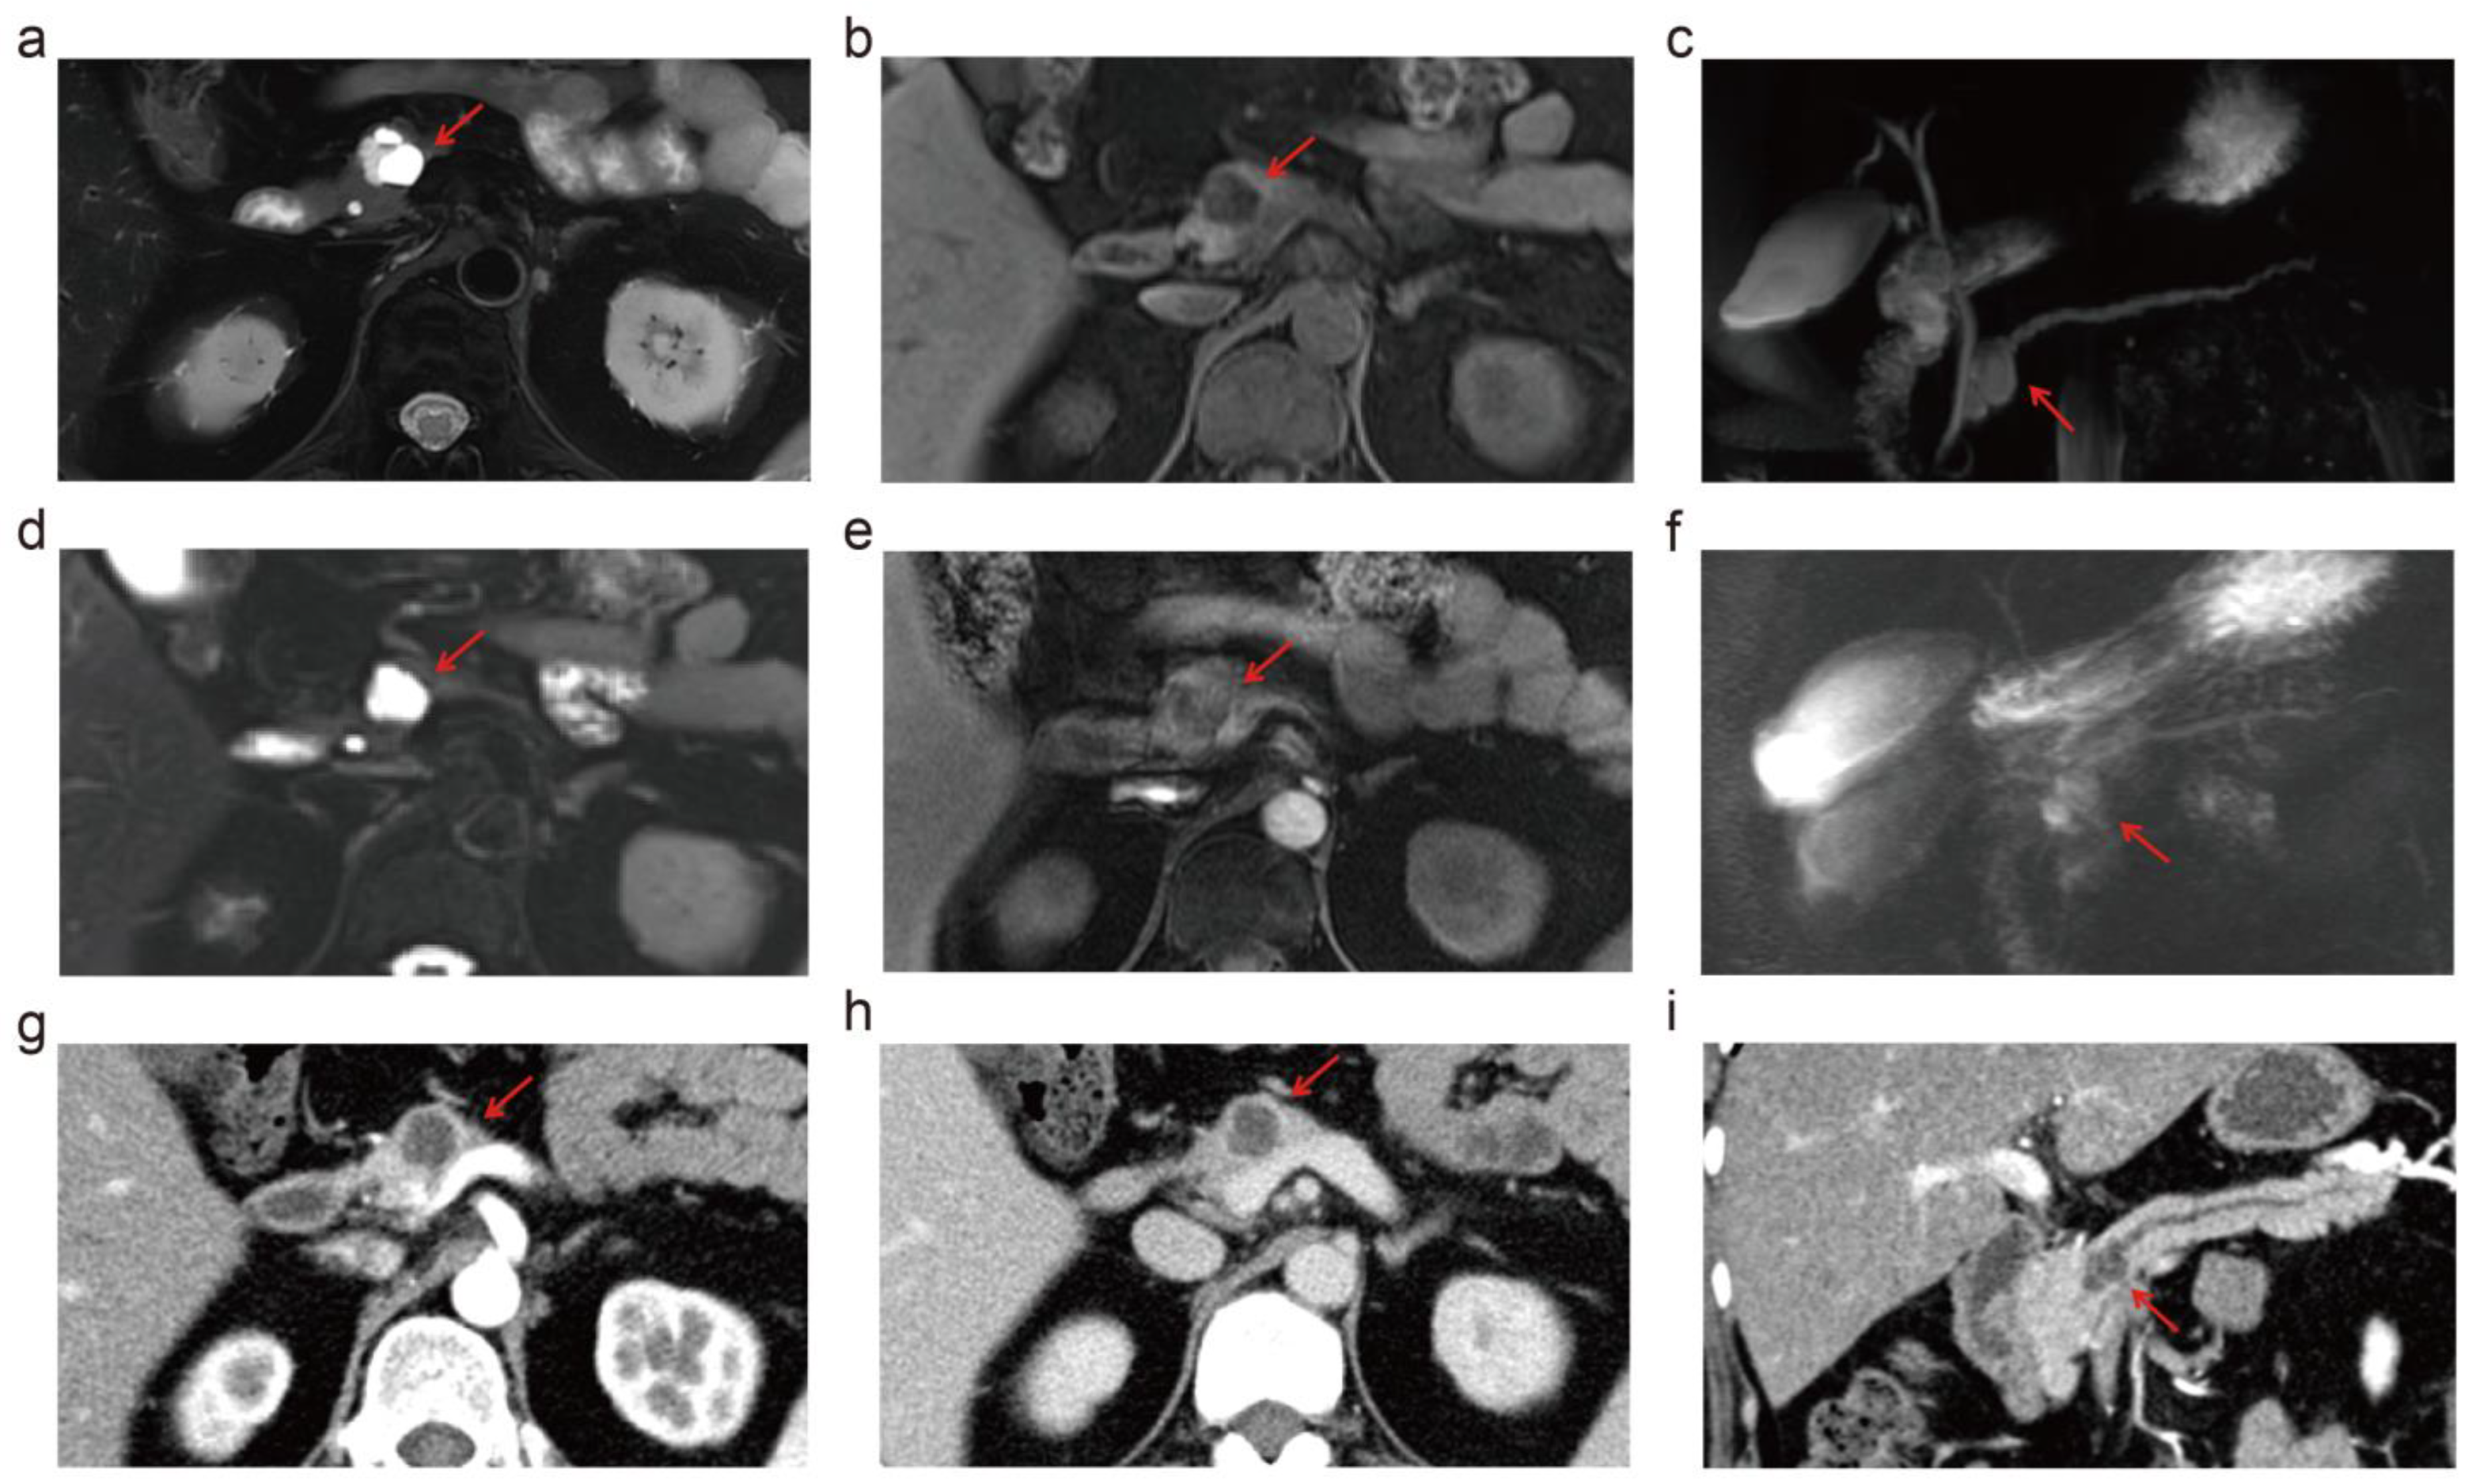

3.3. Depiction of PCL Imaging Features: 5.0 T vs. 3.0 T vs. MDCT